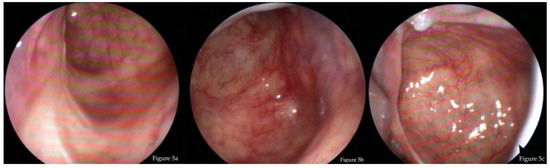

3.3. Endoscopic Findings